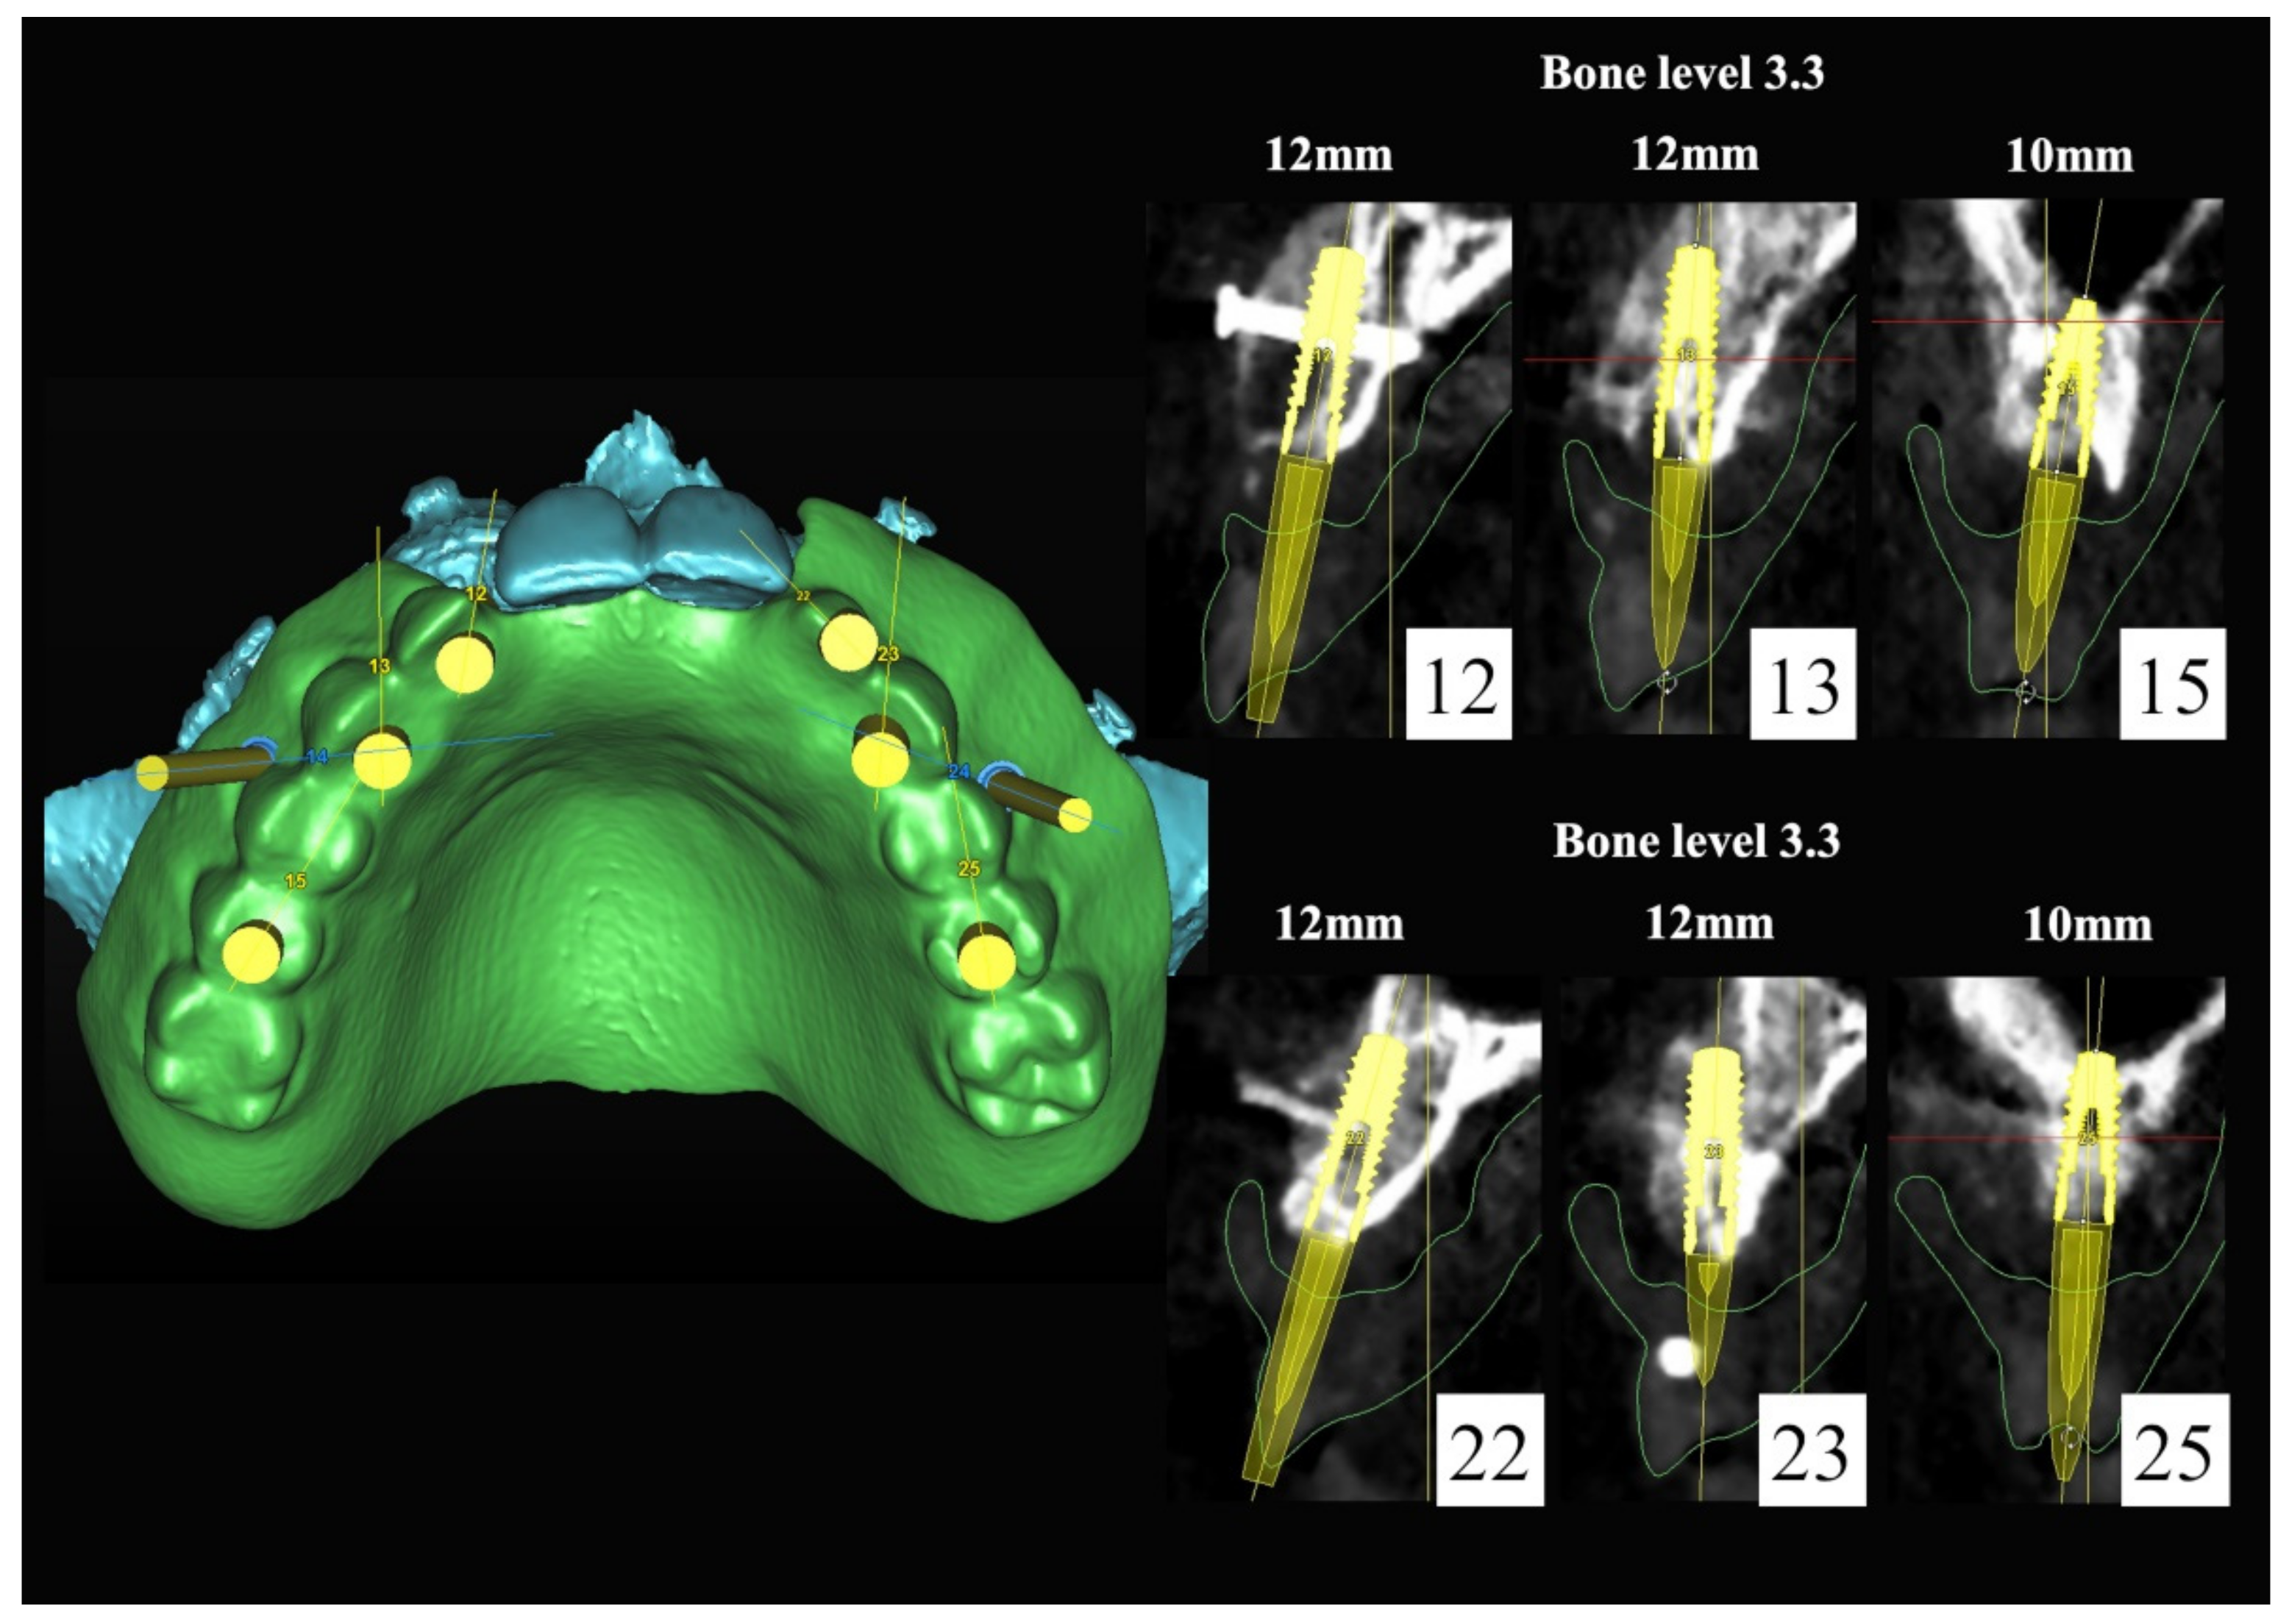

The number, the length, the diameter and the placement of computational virtual implants were determined with respect to the design of the final prosthesis the available residual bone volume and the anatomical limitations according to the previously described technical procedure (Figure 16, Figure 17, Figure 18, Figure 19, Figure 20 and Figure 21).

Figure 16.

Three-dimensional (3D) CBCT scan images with the patient wearing the planned prosthesis.

Figure 18.

Three-dimensional (3D) planning of the number, the diameter and the axis of dental implants with respect to the design of the final virtual maxillary prosthesis.

Figure 19.

In March 2013, twelve guided dental implants were placed at sites # 12, # 13, # 15, # 22, # 23, # 25, # 33, # 34, # 36, # 43, # 44, and # 46 (Figure 22, Figure 23, Figure 24, Figure 25 and Figure 26)